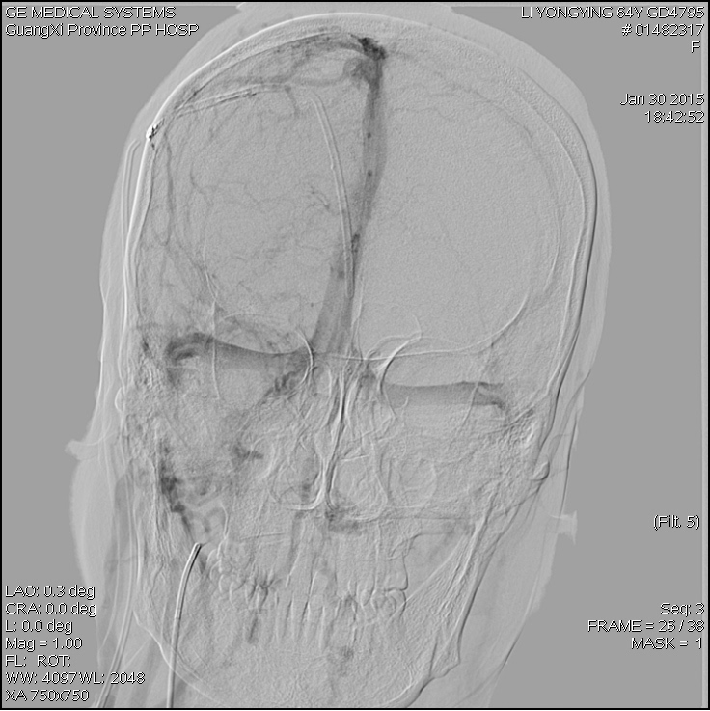

2015-1-30 DSA

脑压为60mm水柱

低颅压原因?(分流泵故障?脑顺应性差?

2015-2-1

在局麻下行腰椎穿刺术+ 测脑压术,患者取左侧卧位,测量脑脊液压力为60mm水柱。